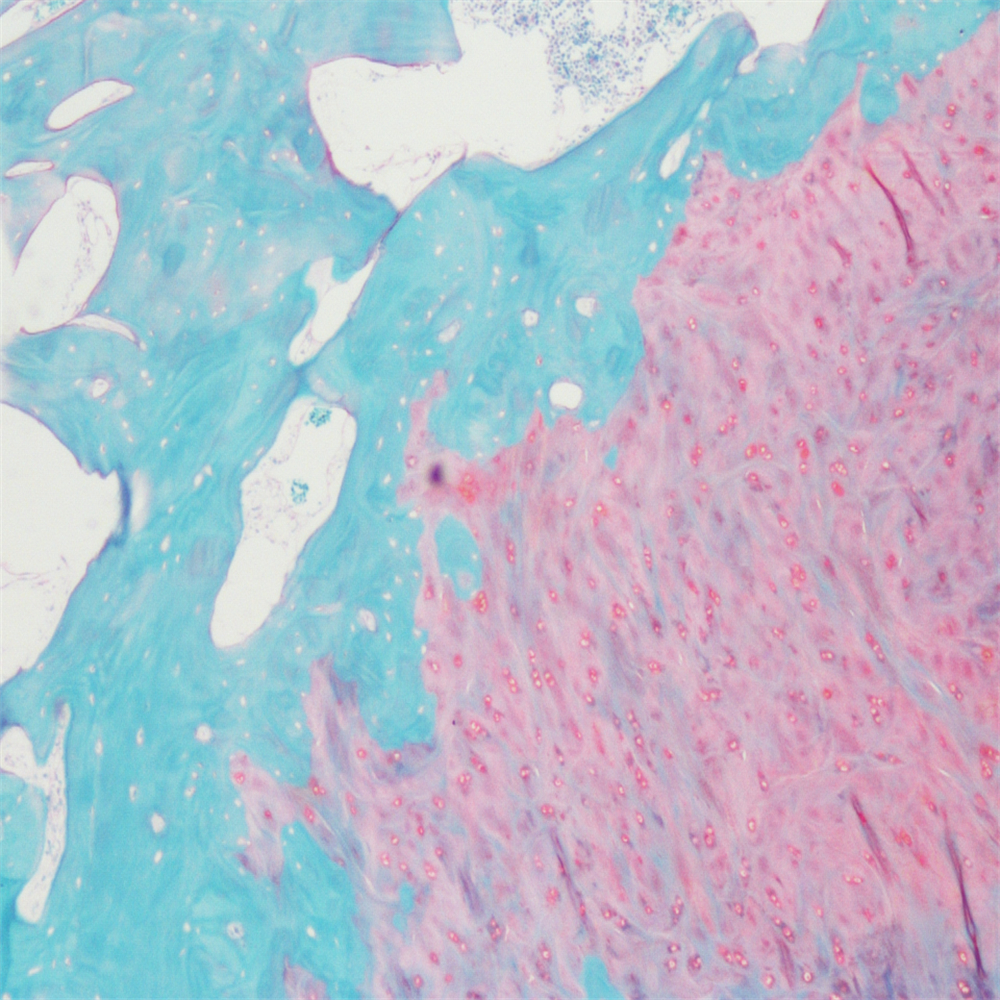

番红-固绿染色

番红-固绿染色(软骨)在涉及关节软骨及软骨下骨的形态学研究中,常需联合使用多种染料以显示其组织学结构。其中,起源于上世纪60年代的番红O(safranin O)-固绿(fast green)染色因可以直观反映关节软骨、软骨下骨和骨组织的结构而备受青睐。软骨呈红色,成骨呈绿色。

番红-固绿(软骨)染色法的染色原理在于嗜碱性的软骨和碱性染料番红O结合呈现红色,嗜酸性的骨和酸性染料固绿结合而成绿色或者蓝色,与呈现红色的软骨对比鲜明,从而将软骨组织和骨组织区分开。番红O是一种结合多阴离子的阳离子染料,其显示软骨组织是基于阳离子染料与多糖中阴离子基团(硫酸软骨素或硫酸角质素)结合。番红O着色与阴离子的浓度近似成正比关系,间接反映基质中蛋白多糖的含量和分布。当软骨收到损伤时,软骨中的糖蛋白会释放出来,使基质成分分布不均匀,从而导致番红O淡染或不着色。通过图像分析软件可以对番红O染色的软骨基质进行定量分析。固绿与胶原纤维结合,不宜褪色。

实验结果展示:

<番红固绿-骨>